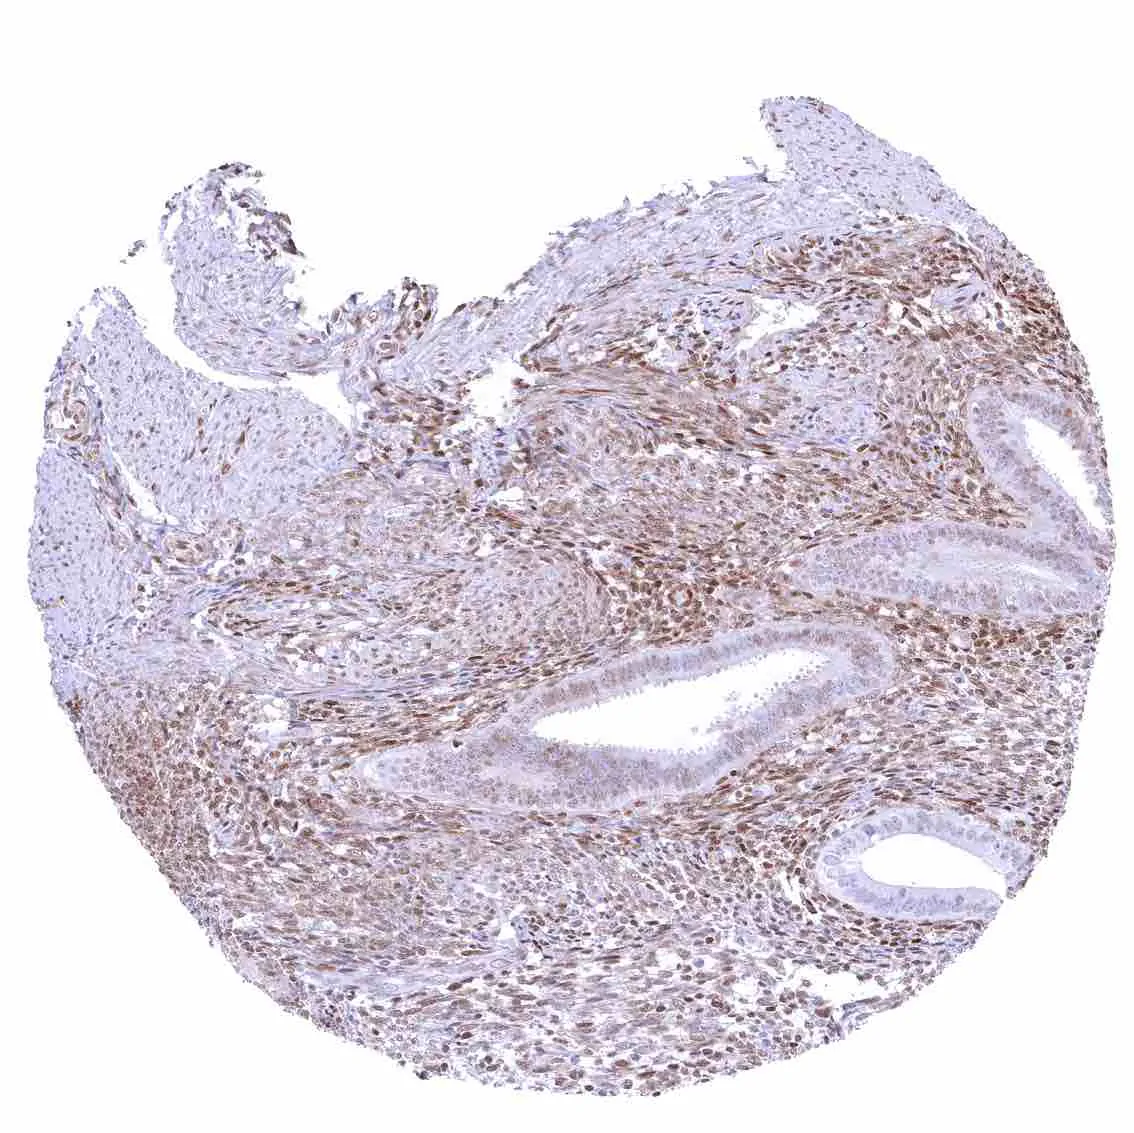

Tonsil – Strong nuclear p27 staining of a significant subset of cells, especially in the interfollicular area. Nuclear staining of squamous epithelial cells predominates in the more mature cell layers (top 50_ of the epidermis).

Tonsil, surface epithelium – Strong nuclear p27 staining of a significant subset of cells, especially in the interfollicular area. Nuclear staining of squamous epithelial cells predominates in the more mature cell layers (top 50_ of the epidermis).